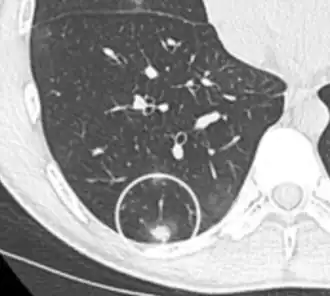

-

Low attenuating nodule (in this case a fat containing hamartoma).[9] -

Cavitation with relatively thick wall, in this case aspergilloma).[9]